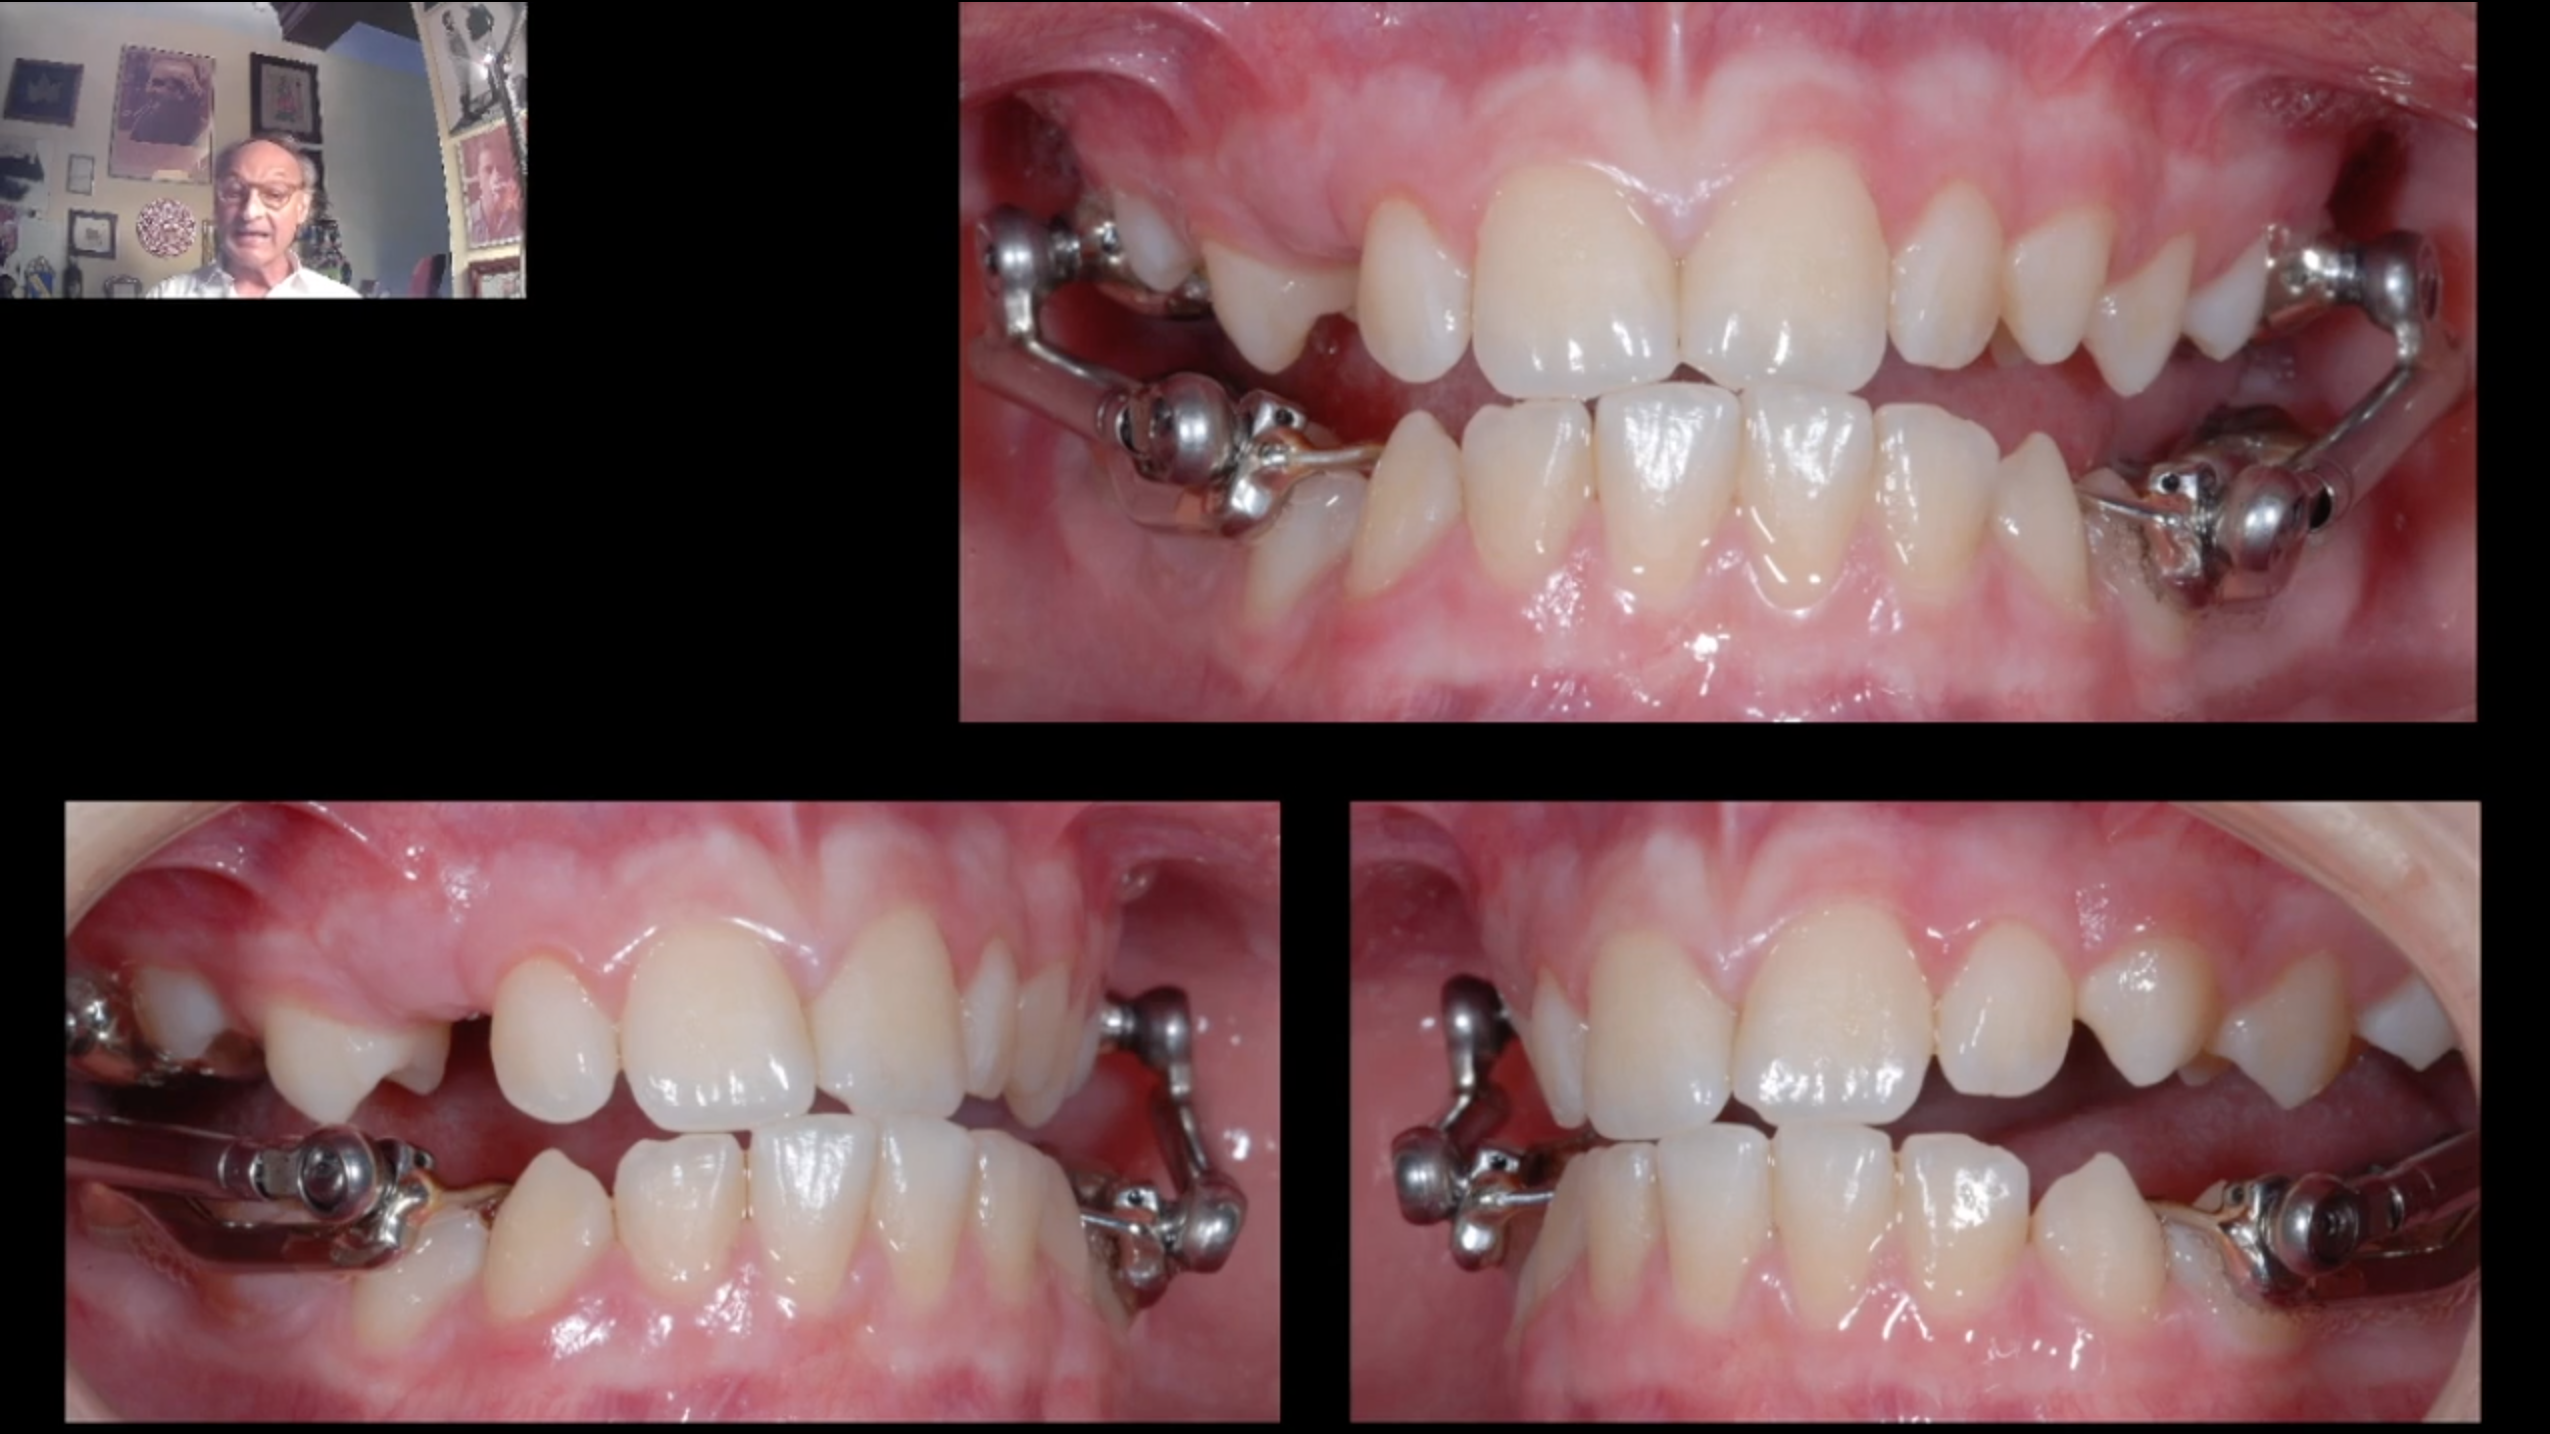

L’apparecchio di Herbst rappresenta attualmente il “gold standard” nel trattamento delle malocclusioni di classe II.

È l’apparecchio “non compliance” per eccellenza ed essendo, le malocclusioni di Classe II, le più frequenti nei nostri studi, ne è evidente l’assoluta importanza nel bagaglio terapeutico di ogni ortodontista.

- Come usare in sicurezza l’apparecchio di Herbst

- Come stabilizzare l’apparecchio di Herbst